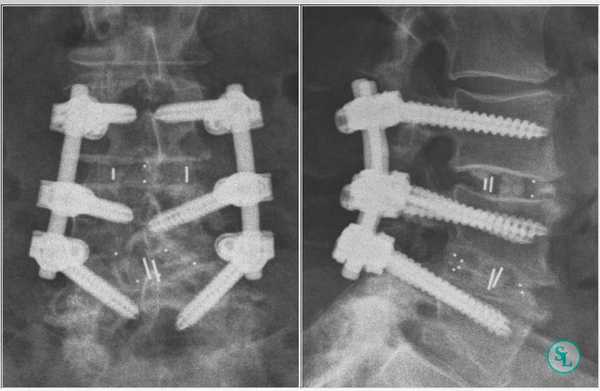

В. Рентгенограмма в положении стоя в боковой проекции — спондилолистез L3-L4 первой степени и дегенеративные изменения замыкательных пластинок. Послеоперационные рентгенограммы в прямой (слева)

и боковой (справа) проекциях после прямого бокового межтелового спондилодеза L3-L4 и минимально инвазивной транспедикулярной стабилизации позвоночника. Аксиальный МР-скан в режиме Т2:

Рентгенограммы полученные после трансфораминального спондилодеза поясничного отдела позвоночника.